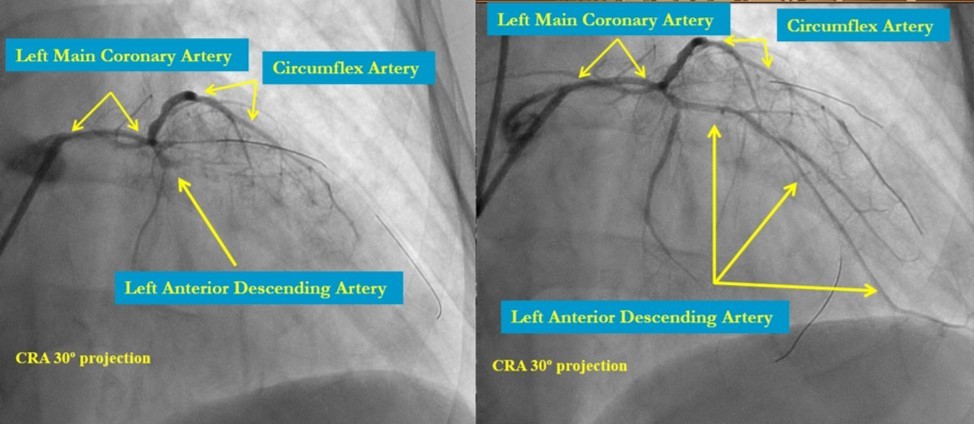

In the first stage, occluded left main and circumflex arteries were recanalized utilizing the support-balloon technique, and CTO wires (Miracle 3™ wire, Abbott Vascular; Runthrough® NS Intermediate wire, Terumo) and balloon pre dilatation was done (Figure 3). In the second stage, the occluded LAD artery was successfully recanalized by utilizing the support-balloon technique, and CTO wires (Figure 3) (due to severe calcinosis the second stage lasted 40 min). In the third stage, LAD artery, CX artery, as well as LMCA and its bifurcation, were stented with 3 drug-eluting stents (Resolute Integrity Zotarolimus DES, Medtronic), the "Culotte Stenting " technique was used for bifurcation stenting (Figure 4), followed by "Kissing Balloon" post-dilatation technique, and finally, proximal optimization technique was performed in the LMCA. The final angiographic image is good, the intervention ended without complications (Figure 5).

Figure 3.LMCA, CX, LAD after recanalization and predilatation